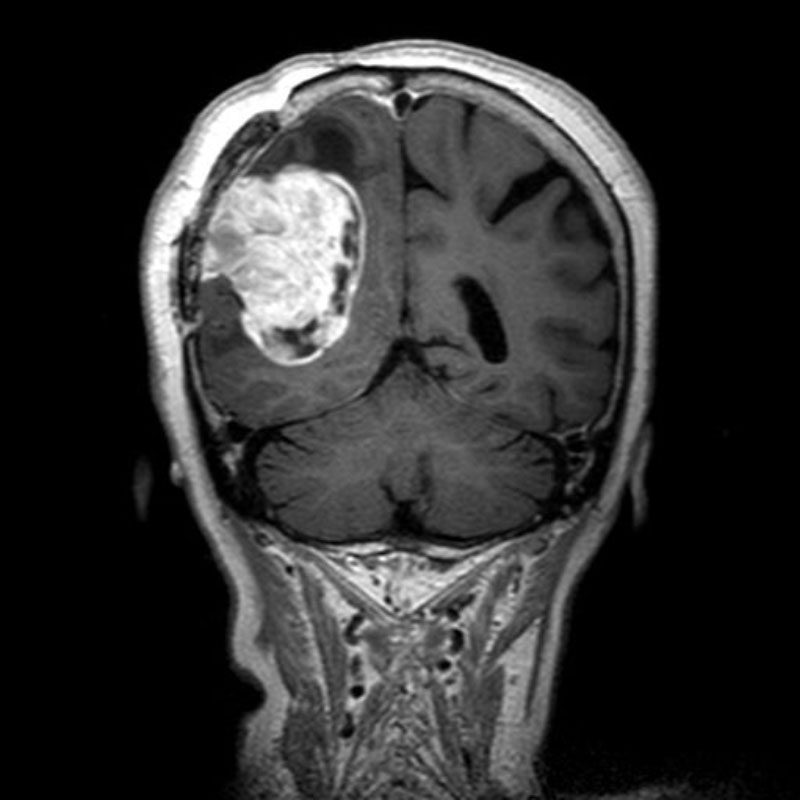

円蓋部髄膜腫

頭蓋内腫瘍摘出術

No.’25_88 手術前1

No.’25_88 手術前2